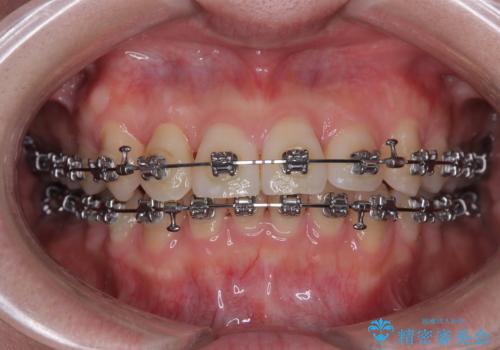

捻転の強い前歯 ワイヤー装置での非抜歯矯正

- 前歯のデコボコ、特に90度捻れている上顎前歯を気にして来院された患者様です。

マウスピースでもワイヤーでも対応可能でしたら、捻転が非常に強いことから、患者様と相談の上ワイヤー装置にて矯正治療を行うこととしました。

捻転を解消する際に、歯列全体が前方に突出して出っ歯の仕上がりとなることが懸念されたため、補助装置を用いて上顎歯列全体を後方に移動する力をかけることとしました。

当初予定通り1年半ほどの治療期間で、非常に綺麗な歯列に仕上げることができました。